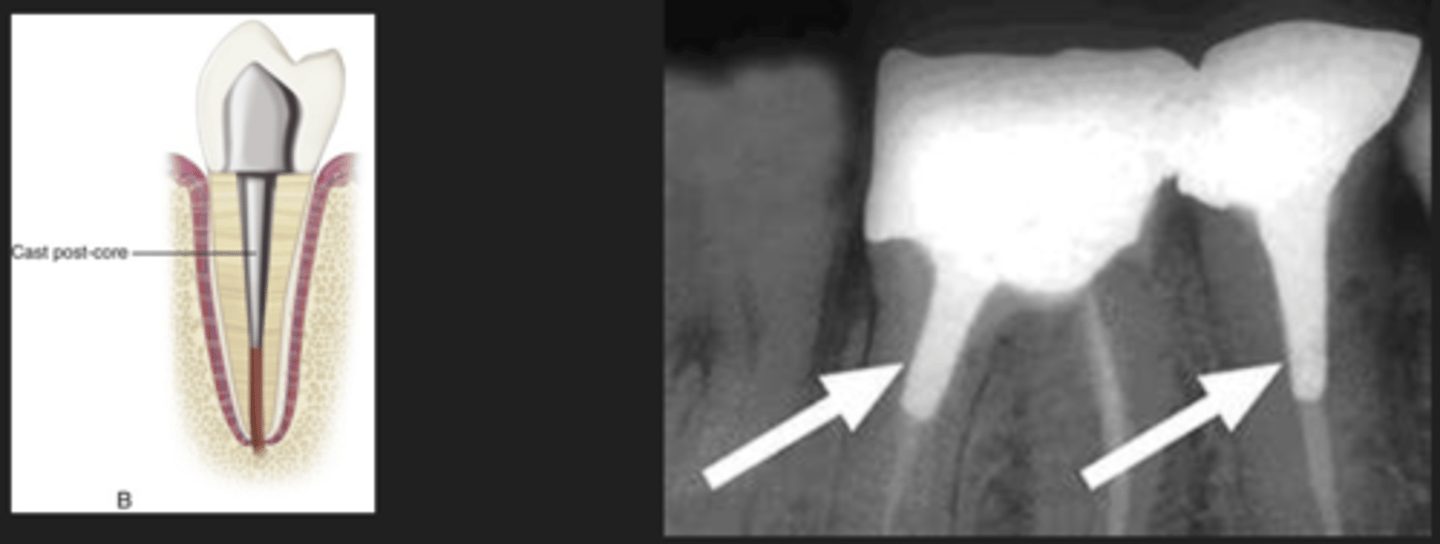

Post and core

- Metallic post and core that is cast at the lab

- Then seated in the root canal system and coronally to support tooth structure

Crown, amalgam, crown, cast post, gutta percha, and silver points location